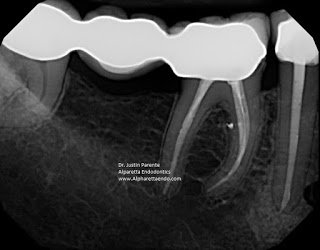

These exits can also be found in the furcation region. If untreated and contaminated with bacteria, they can feed furcation radiolucencies and cause attachment loss (probing). Here is a straightforward #30.